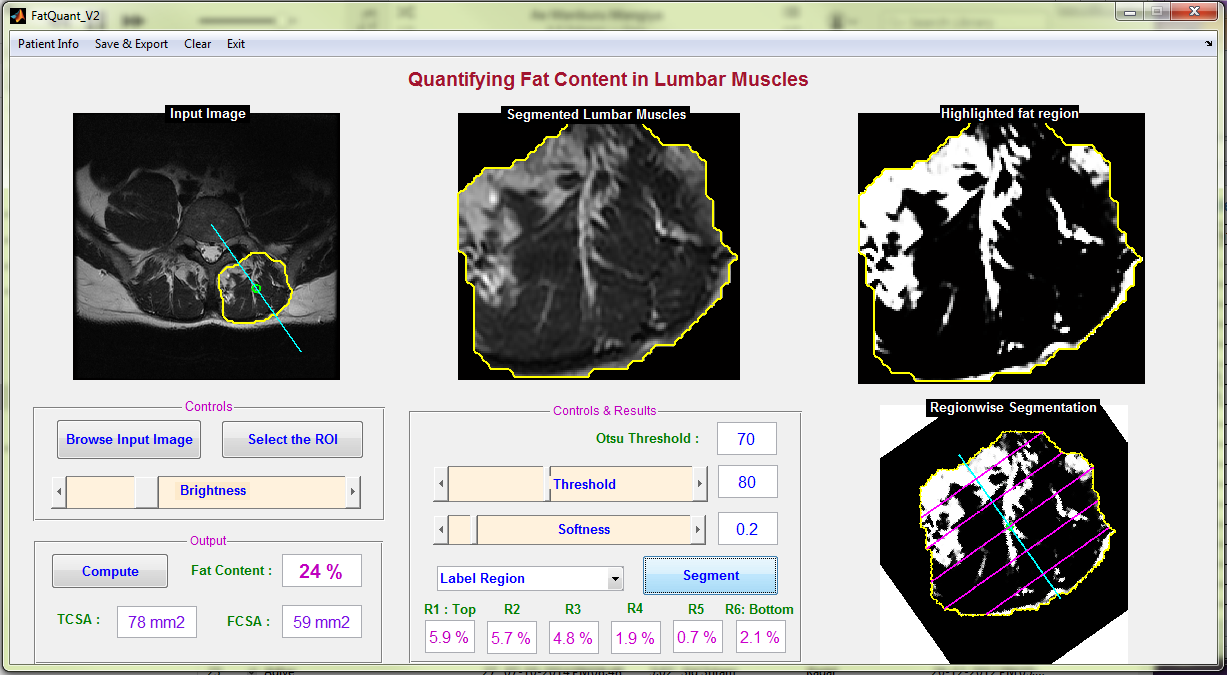

2.2 Interactive segmentation tool

A standalone Graphical User Interface (GUI) shown in Figure 1 using Matlab R2010a was developed with the essential interactive controls. Initially the GUI, allows the user to select an input image. Then the user can define the region of interest (ROI) by plotting a mask using the livewire (intelligent scissors) interactive segmentation technique [21]. Once the mask is created interactively, the ROI is segmented and the grayscale image is displayed in the GUI. The global threshold to convert the grayscale image into a binary image is calculated using Otsu’s method [28]. By default the threshold value is set at Otsu’s threshold and the softness value is set at 0.2 (this value is based on empirical investigation). The softness value is mainly used for improving the visual clarity of fat regions by smoothing the edges of fat regions. For incremental variation of softness value in the steps of 0.1 from values 0 to 0.5, the fat percentage varies from 0.2 to 2 and the cross sectional area varies upto 3 . Initially, with pre-defined threshold and softness, the fat regions are identified from the segmented lumbar muscle and displayed in the GUI. Based on visual inspection, suitable values for threshold and softness can be fixed by adjusting the ‘Threshold’ and ‘Softness’ sliding controls respectively. The ‘Brightness’ sliding control allows the user to adjust the brightness of the input image for better visualisation.

The total fat content percentage, total cross-sectional area (TCSA) and functional cross-sectional area (FCSA) in can be calculated at any stage by pressing the ‘Compute’ button. The computation of fat content percentage, TCSA, and FCSA is performed in line with the previous studies [5, 2, 4, 25].

By using the drop down menu ‘Label Region’ the user indicates the region of interest. The list of regions included in the menu are Right Erector Spinae muscles, Left Erector Spinae muscles, Left Lumbar Multifidus Muscles, Right Lumbar Multifidus Muscles, Right Psoas Muscles, and Left Psoas Muscles.

The Erector Spinae (ES) Muscle is sub-divided into six fragments at equal intervals with reference to the center of spinal column and fat in each region is quantified. The center of spinal column is automatically detected for a given input image. The region wise quantification of fat in the ES muscles, either on left or right side of the spinal column, is carried out by selecting ‘Segment’ in the GUI. The ES muscle fragments are labelled R1 to R6 from top to bottom respectively, the fat percentage in each region is computed and displayed in the GUI.

The GUI was iteratively developed based on feedback from experts. The GUI includes the Otsu’s threshold set as the initial reference, variable-selection of threshold and softness levels, computation of total and functional cross-sectional area, region-wise fragmentation of the ES muscle with reference to the centre of spinal column, which were based on experts opinion.

3.4 Graphical User Interface

A screen shot of the graphical user interface (GUI) captured while quantifying fat in erector spinae muscles is shown in Figure 13.